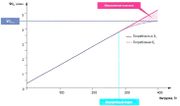

| 09:46, 20 июля 2016 | Mishci sport89.jpg (файл) |  |

15 КБ | Anes | Определение анаэробного порога при велоэргометрии. Анаэробный порог — максимальная нагрузка, при которой концентрация лактата в крови… | 1 |